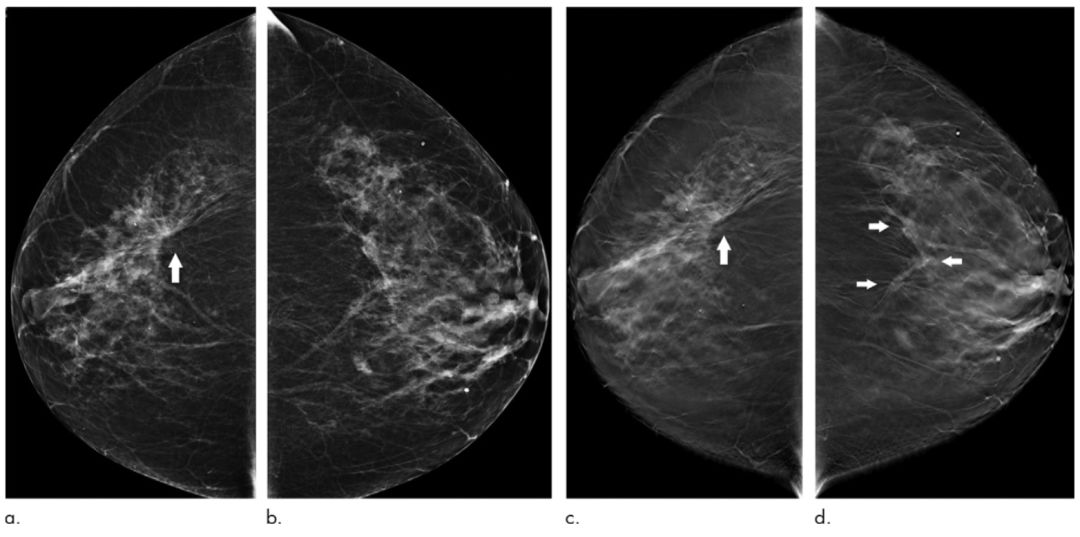

图 3.4 73岁女性的双乳DM(a,b)及DBT(c,d)

注:a中右侧乳房外上象限箭头所示的结构扭曲是浸润性小叶癌,这一变化在c中同样可以被检测到;b中的左侧乳房并未发现可疑的病变,但在d中则能发现左侧外下象限的病变。